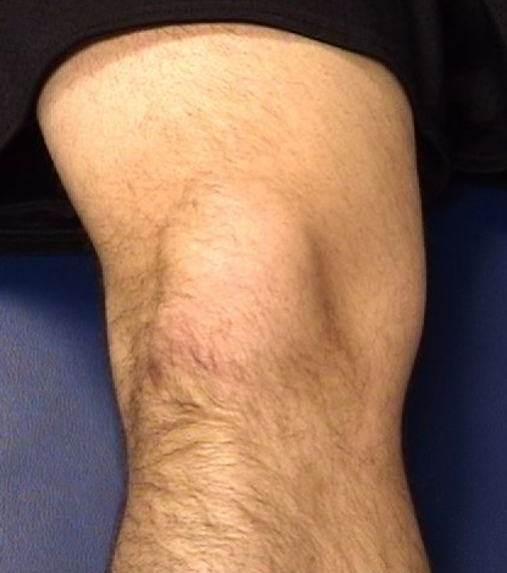

Knee: Patellar Instability

etiology and presentation

A

Etiology:

Medial or lateral subluxation or dislocation of patella; often related to loose or torn retinaculum (MPFL) or muscle weakness

Presentation:

Depends on severity of injury

Pain, swelling, “kneecap popped out of socket”

Non-contact twisting injury w/ knee & foot externally rotated

13

Q

PE and Dx

PE:

Chronic: sometimes can manipulate patella to sublux – patellar translation

Acute: Traumatic Effusion

If dislocated, it will be visible

TTP at medial* or lateral edge of patella

Diagnosis:

X-rays and MRI to see location, inflammation, loose bodies, MPFL tears